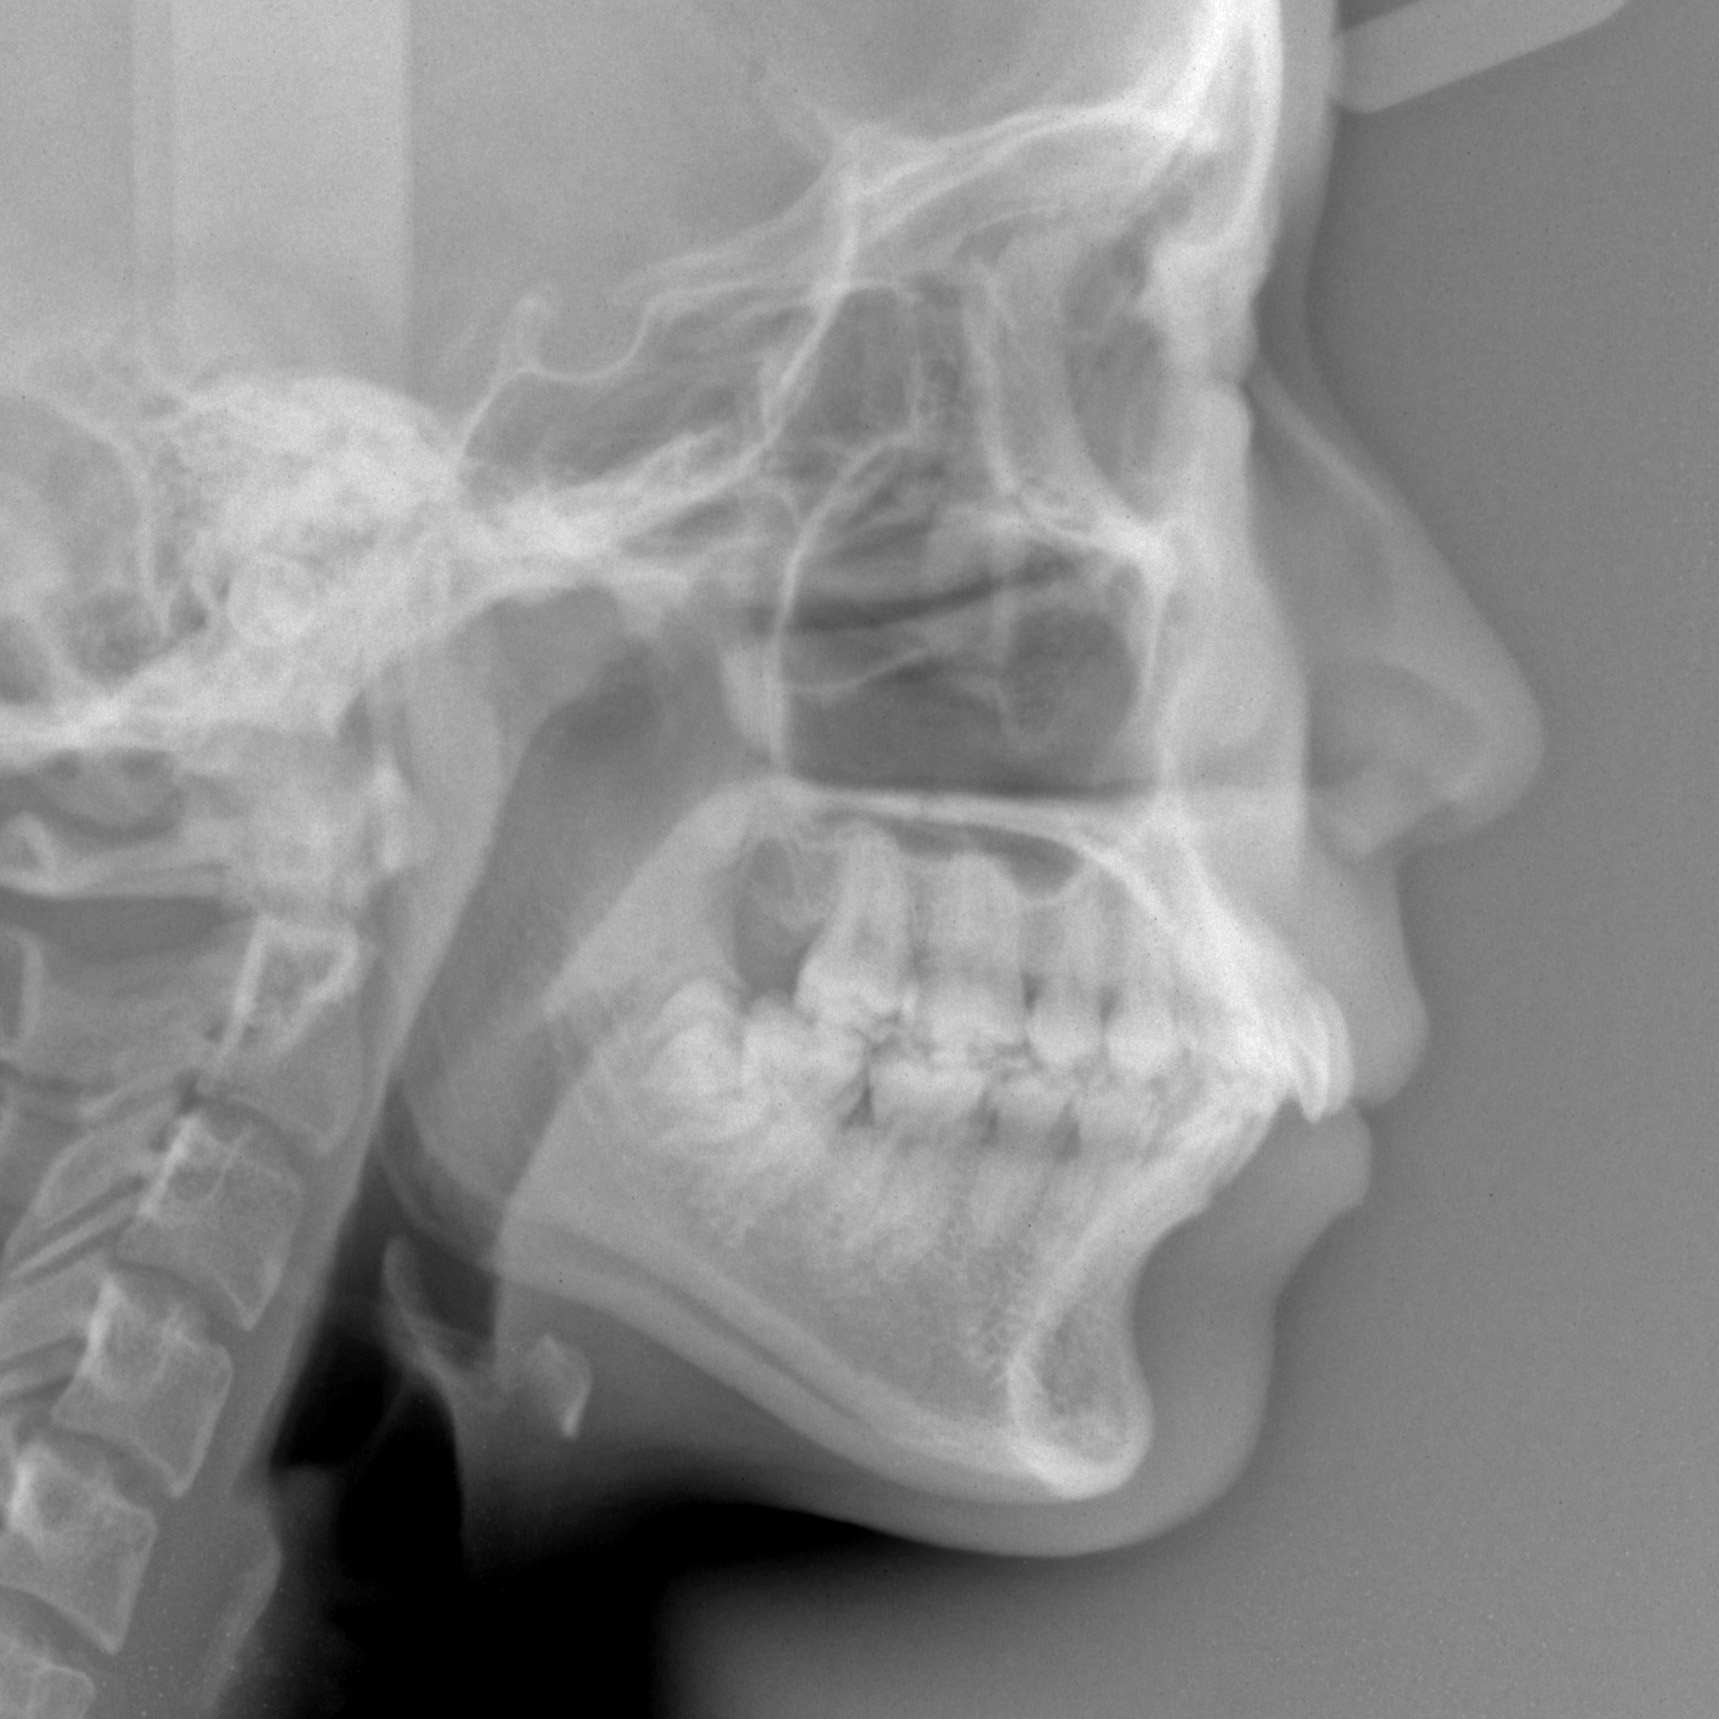

新着情報 1370 治療前セファロ側面 Tweet 投稿日 : 2024年01月31日(水)カテゴリー : コメントを残す コメントをキャンセルメールアドレスが公開されることはありません。 * が付いている欄は必須項目ですコメント 名前 * メール * サイト 19歳 女性「 出っ歯、口もと を 治してほしい」治療期間19か月(上下顎前突症) ≫